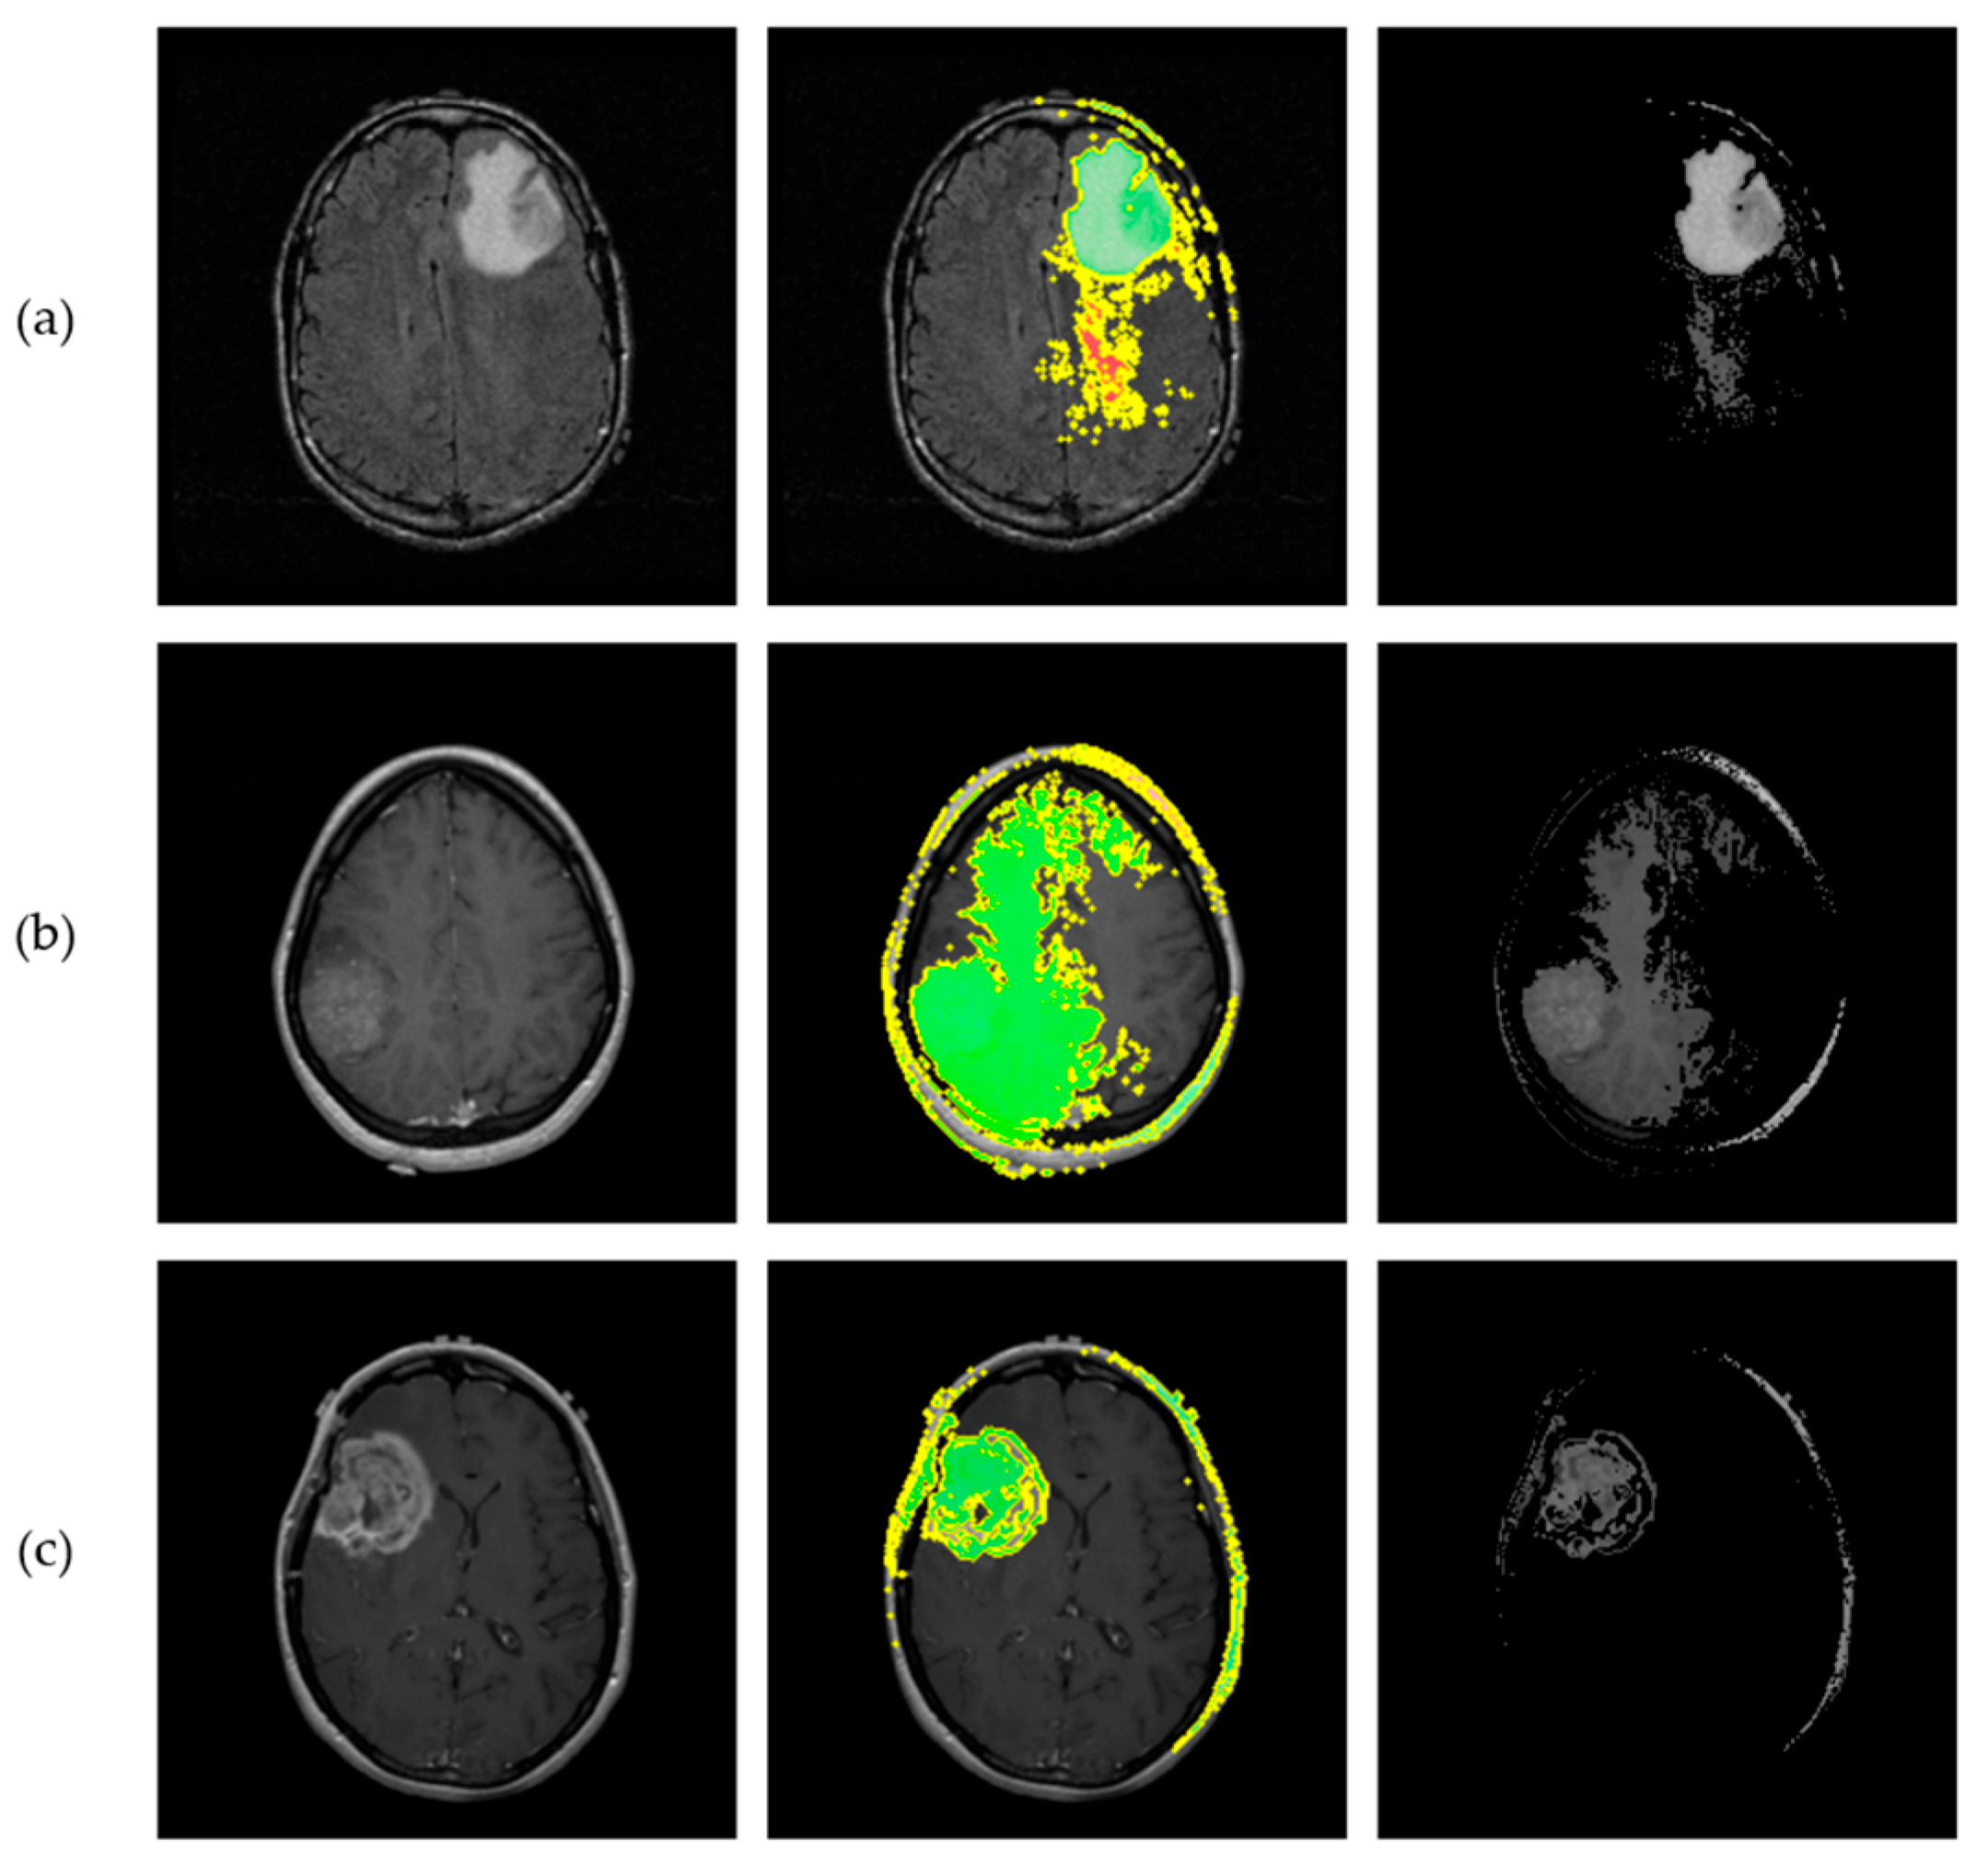

The SHAP model was applied to interpret the network’s decisions, utilizing the Shapley values to provide both local and global explanations, thereby assessing the overall system’s performance. The number of evaluations was fixed to 50,000, ensuring an accurate and comprehensive evaluation of the model’s decision-making process. Figure 14 illustrates the application of SHAP, where the proposed CNN classified one representative test sample from each astrocytoma grade (G2–G4). For each input slice, SHAP visualizations were generated for all three possible tumor grades, enabling a detailed understanding of the network’s behavior. In these visualizations, red areas represent 2D cross-sectional regions with a positive contribution toward the predicted class, while blue areas include features that correspond to other classes’ slice characteristics, indicating a negative correlation. The intensity of the red and blue colors reflects the strength of these contributions.

LIME was subsequently employed as a heuristic Explainable AI tool to interpret the proposed CNN’s predictions. To generate local explanations, LIME segmented each 2D slice into superpixels and produced 20,000 perturbed samples per instance. The analysis focused on the three most influential regions contributing to each prediction. LIME then visualizes these regions by applying a green or red color overlay, indicating whether the region contributes positively or negatively to the predicted class, respectively. Additionally, a masked version of the original slice was produced, where only the most influential regions were retained, offering a clear view of the areas contributed to model’s decisions. Figure 15 illustrates the application of LIME algorithm on the same representative astrocytoma samples used in the SHAP analysis.

Figure 14. SHAP visualization illustrating the influence of slice pixels through the proposed network, providing transparency on astrocytoma grading. (a) Visualization of a Grade 2 astrocytoma sample; (b) Grade 3 astrocytoma; (c) Grade 4 astrocytoma. For each case, SHAP values are presented for all three possible class predictions. Red regions indicate positive contributions toward the predicted class, while blue regions indicate negative contributions associated with features of other grades. Color intensity reflects the magnitude of each pixel’s influence.

Figure 15. Results from implementation of the LIME algorithm, illustrating the local contributions identified by the proposed CNN and offering interpretability for the astrocytoma grading process. Each row corresponds to a different tumor grade. (a) Visualization of a Grade 2 astrocytoma sample; (b) Grade 3 astrocytoma; (c) Grade 4 astrocytoma. From left to right: original MRI slice, LIME explanation highlighting the top 3 contributing regions, and masked original slice where only the top regions are retained. Green and Red colors indicate positive and negative contribution of the corresponding “superpixels” for class prediction, respectively.